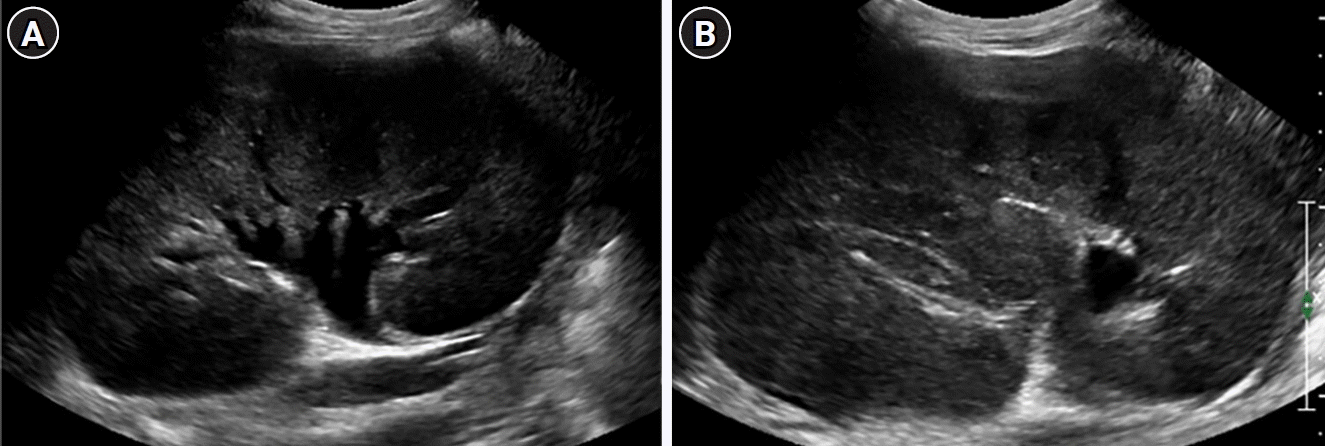

Fig. 4.

Ultrasound images of the right (A) and left (B) kidneys reveal diffuse enlargement of both kidneys, along with heterogeneous hyperechogenecity in the renal cortices.